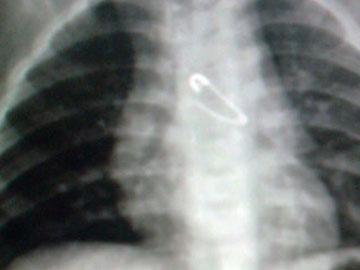

Trước đó, bệnh nhân liên tục đau bên hạ sườn trái kéo dài 2 tuần mà không rõ nguyên nhân. Khi thăm khám tại một trung tâm y khoa, bác sĩ phát hiện dị vật có hình nhọn cắm vào rốn lách, nguy cơ xuyên thủng động mạch lách.

Cây tăm ghim thủng lá lách được chụp bằng ảnh nội soi. Ảnh: BSCC